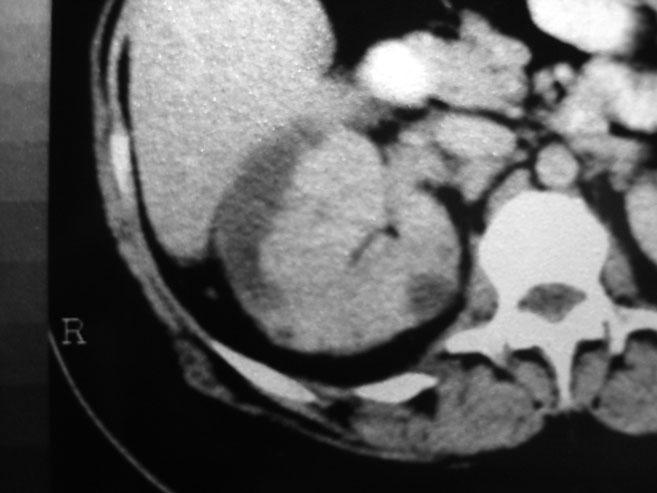

Chronological Photo-sequence

of the case progression

-After 2 months of presentation and treatment:

![]() |